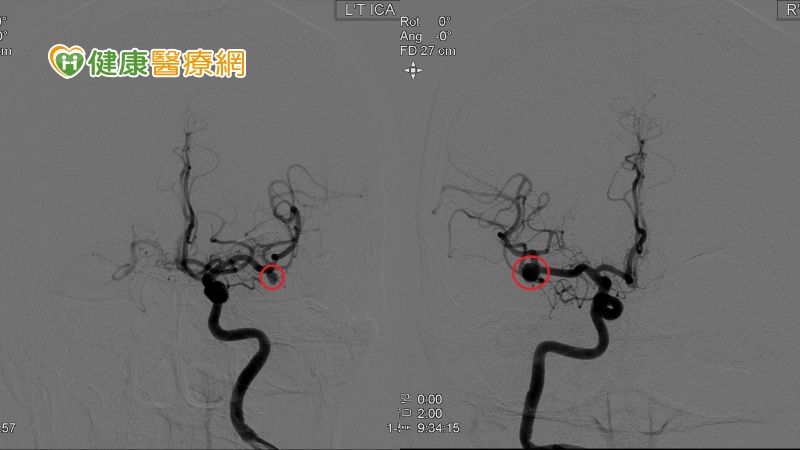

▲術前血管攝影顯示,陳女士出現左側0.3與右側0.5公分中大腦鏡像動脈瘤。

一位61歲陳女士頭暈不適長達2年,經核磁共振檢查發現其中大腦動脈出現「鏡像動脈瘤」,對稱分布於顱內中線兩側對應血管的動脈瘤。根據神經外科雜誌《Journal of neurosurgery》研究指出,女性相較於男性更容易患有鏡像動脈瘤,且集中於40歲至70歲年齡層。陳女士進行2次開顱夾閉手術夾閉動脈瘤,術後暈眩狀況恢復良好,觀察後順利出院。

徐賢達說明,中大腦動脈瘤屬於寬頸瘤,其開口較大,因此開顱夾閉手術是較為理想的選擇。手術時須移除頭蓋骨,以鈦合金動脈瘤夾夾住動脈瘤根部,阻斷血液滋養它長大,手術成功後復發率幾近於零。順利夾閉後再透過術中血管攝影與血管超音波即時檢查,避免夾閉不全或是壓迫到周圍血管。